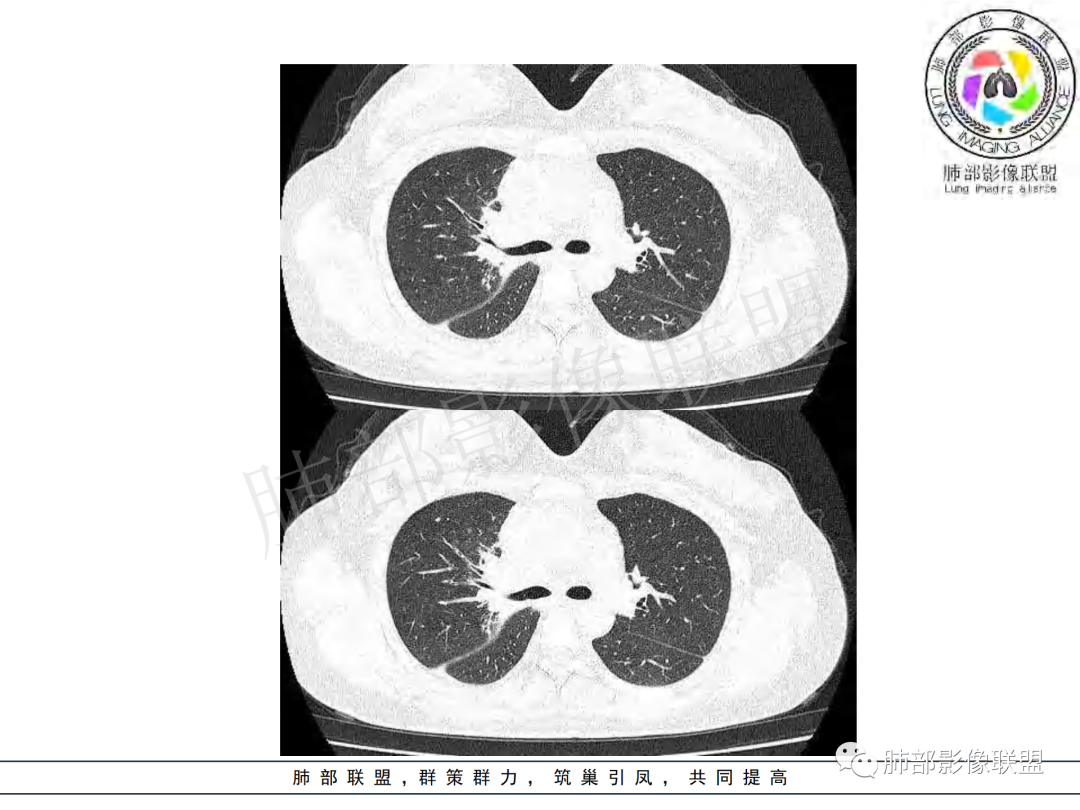

纵隔多组及右侧肺门多发肿大淋巴结,部分融合,不均匀强化,内见斑片状坏死区及环状强化,后者坏死边界尚清晰,肺门区肿大淋巴结与肺组织边界不清,年轻女性,8个月病史,发热首发症状,考虑淋巴结核并向肺内侵及(破溃?),鉴别淋巴瘤

女,20,病程长达8月,发热、胸痛、右侧胸腔积液病史。胸部CT:右肺门旁不规则肿块影,右中间支气管腔内结节,纵隔多发淋巴结肿大;强化不均匀,灶性坏死灶,环形强化;右侧少量胸腔积液并局部肉芽肿样突起。年轻女性,长病程,多部位,考虑慢性炎症,结核?鉴别肿瘤。

支气管腔内有占位,肺门区病灶和胸膜结节明显强化,淋巴结环状强化为主,部分明显强化,年轻女性,首先考虑结核,鉴别腺癌

青年女性,发热、胸痛、右侧胸腔积液病史,病程8个月。曾多次抗炎后均有好转。CT:右肺门旁肿块影,双侧胸膜结节,纵隔多发淋巴结肿大,边缘模糊;增强渐进性明显强化,纵膈淋巴结较彻底坏死灶,边缘环形强化。考虑结核,鉴别恶性肿瘤。

女性,20岁。高热、畏寒。右肺上叶近肺门区不规则肿块,周围斑点、片小结节影伴肿大淋巴结,肿块包绕并突入右主支气管腔内,增强后肿块不均匀强化,淋巴结环形强化中心低密度,考虑结核。

本例患者,年轻女性,慢性病程,多次抗感染治疗效果不佳,实验室检查示白细胞及中性粒细胞不高,不支持普通细菌感染,虽然肺泡灌洗液X-Pert检测阴性,结合患者胸部CT结核感染亦不能排除,胸部CT主要表现为右侧肺门及纵隔淋巴结肿大,仔细观察不难发现右中间支气管内新生物凸向管腔内,增强扫描,右肺门(10R)及纵隔淋巴结(2R,4R)明显不均匀强化,内部呈不规则低密度无强化区,被周边高强化区包绕(环形强化)的特点,首先应当想到纵隔淋巴结结核诊断。淋巴结分布亦不符合肺部恶性肿瘤迁徙途径。